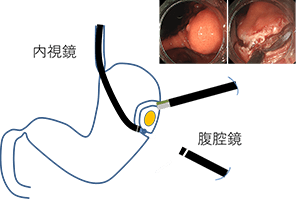

内視鏡医による内視鏡手術と外科医による腹腔鏡手術の合同手術で主にGISTなどの粘膜下腫瘍の治療に行う、低侵襲治療です。手術室(全身麻酔下)で行います。